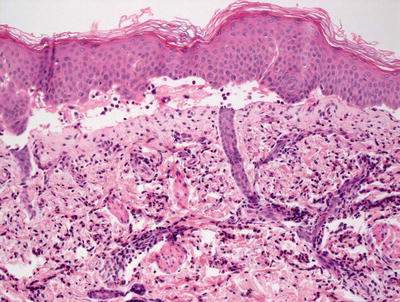

3.8.2 Histology

The histologic findings in hydroa vacciniforme are not specific. The epidermis is markedly spongiotic in early lesions, progressing to reticular degeneration and ultimately necrosis in later stage lesions (Fig. 3.17). Within the dermis, there is a brisk infiltrate that consists predominantly of lymphocytes and histiocytes (Figs. 3.18 and 3.19). Eosinophils are not abundant. Neutrophils may be observed in ulcerated lesions, but this is likely a secondary phenomenon.

Fig. 3.17

Hydroa vacciniforme demonstrates a subepidermal blister with abundant dermal edema and a brisk inflammatory infiltrate

Fig. 3.18

A brisk inflammatory infiltrate in the dermis extends into the overlying epidermis in hydroa vacciniforme. Blister formation is due to spongiosis and can be at any level

Fig. 3.19

Hydroa vacciniforme is characterized by a brisk superficial and often deep dermal inflammatory infiltrate

The histologic differential diagnosis in early lesions or mild cases includes spongiotic processes, such as atopic dermatitis and nummular eczema. As the degree of epidermal edema increases, other entities, such as polymorphous light eruption and herpetic dermatitis, enter the differential diagnosis. Polymorphous light eruption does not ordinarily result in epidermal necrosis, and the inflammatory infiltrate is often deeper and not quite as intense as that seen in hydroa vacciniforme. The marked papillary dermal edema seen in some cases of polymorphous light eruption might also help with this distinction. Herpetic infection demonstrates the same reticular degeneration that characterizes florid cases of hydroa vacciniforme, but keratinocyte multinucleation, nuclear molding, and viral inclusions seen with herpes infections are not present in hydroa vacciniforme. There have been several reports of cutaneous T cell and natural killer cell lymphomas that have similar clinical findings [52–55]. In these cases, the cytologic features of the inflammatory infiltrate should help to elucidate the true nature of the process.